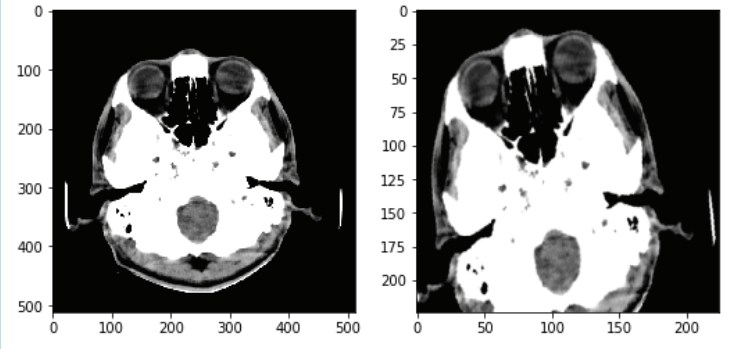

An example can be seen in figure 1